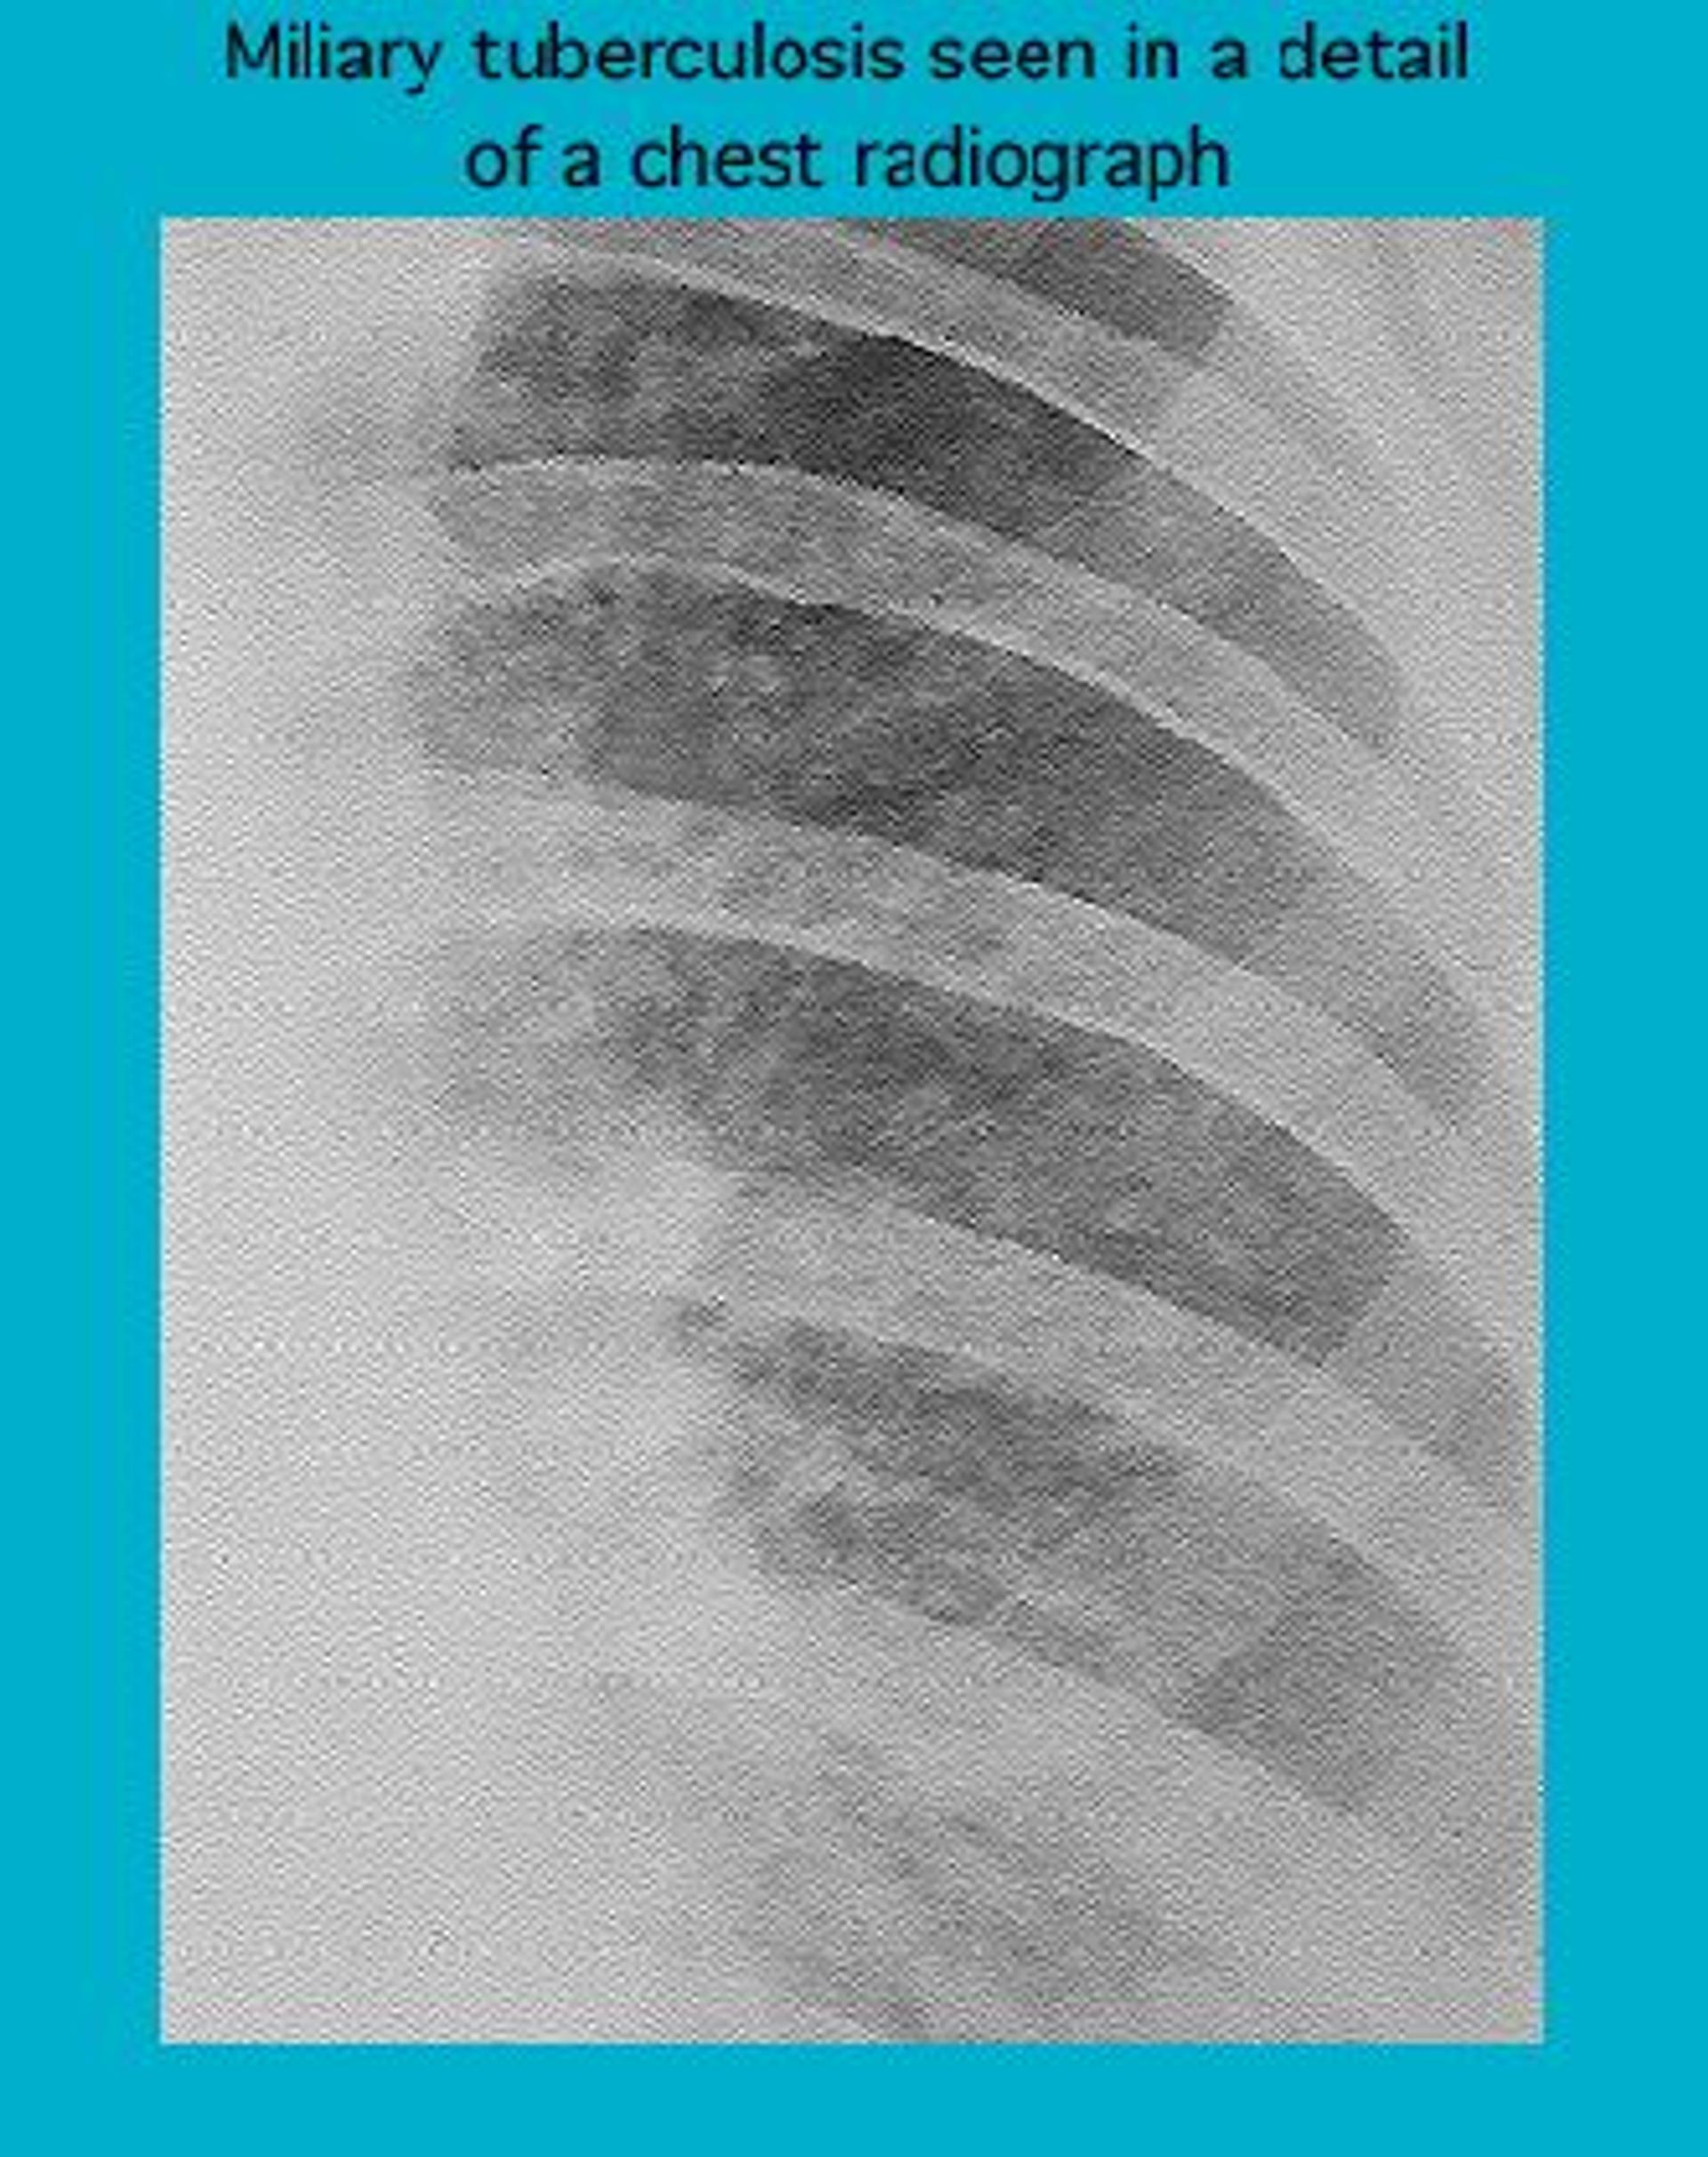

Radiograph of miliary tuberculosis